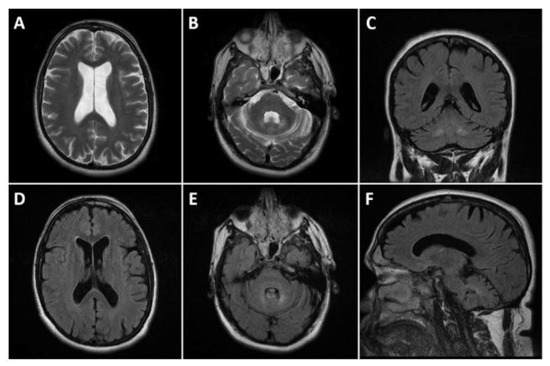

2. Case Presentation